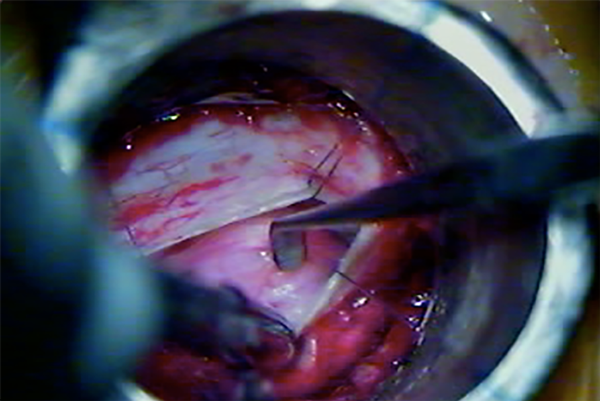

Cuando ya se encuentran en tracción los 4 puntos de reparo dural, los extremos de la incisión se aproximan entre sí, y eso permite incidir con bisturí dichos extremos para realizar una nueva tracción de los puntos de reparo, y así, una mayor exposición lateral (Fig. 7, 8 y 9).

Fig. 7: Ojal dural mediante retracción dural transtubular

Fig. 9: Exposición del contenido intradural mediante retracción dural percutánea.

DISCUSION